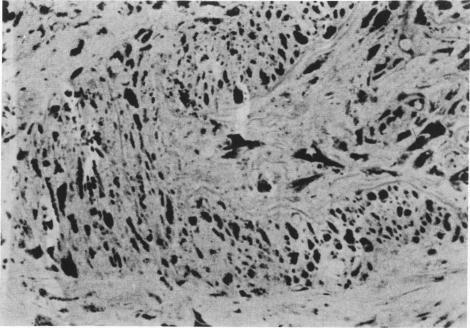

A histochemical study was performed on light- and electron-microscopic level in a case of Fabry's disease. The patient underwent kidney transplantation for renal failure and died of heart failure 6 months later. Patient's tissues were studied at the light- and electron-microscopic levels with various embedding and staining techniques for lipids and carbohydrates. Two peroxidase-labeled lectins (from Ricinus communis and from Bandeiraea simplicifolia) known to have affinity for alpha- and beta-D-galactose, were strongly reactive with the storage material on frozen sections. The ultrahistochemical and extraction tests showed that the typical granules had a variable reactivity and morphologic characteristics in different cells, probably reflecting different composition. A small number of typical deposits were also observed in the transplanted kidney. This is the first reported case of recurrence of the storage disease in the allograft. Of interest was also the fact that the patient's blood inhibited normal alpha-galactosidase activity, suggesting a possible inhibitor-related mechanism in the pathogenesis of the recurrence.

对一例法布里病患者进行了光镜和电镜水平的组织化学研究。该患者因肾衰竭接受了肾移植,6个月后死于心力衰竭。采用多种脂质和碳水化合物包埋及染色技术,在光镜和电镜水平对患者组织进行研究。两种已知对α-和β-D-半乳糖有亲和力的过氧化物酶标记凝集素(来自蓖麻和单叶豆),在冰冻切片上与储存物质有强烈反应。超组织化学和提取试验表明,典型颗粒在不同细胞中有可变的反应性和形态特征,可能反映了不同的组成。在移植肾中也观察到少量典型沉积物。这是首次报道的同种异体移植中储存疾病复发的病例。同样有趣的是,患者血液抑制了正常的α-半乳糖苷酶活性,提示复发发病机制中可能存在与抑制剂相关的机制。